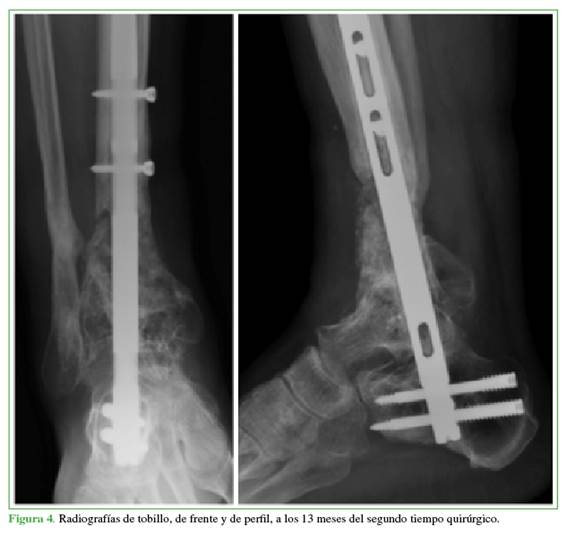

Se realizaron controles clínicos y radiográficos seriados. A los 13 meses del segundo tiempo quirúrgico, se constató la fusión radiográfica y se autorizó la marcha sin asistencia, con retorno a la vida habitual (Figura 4).